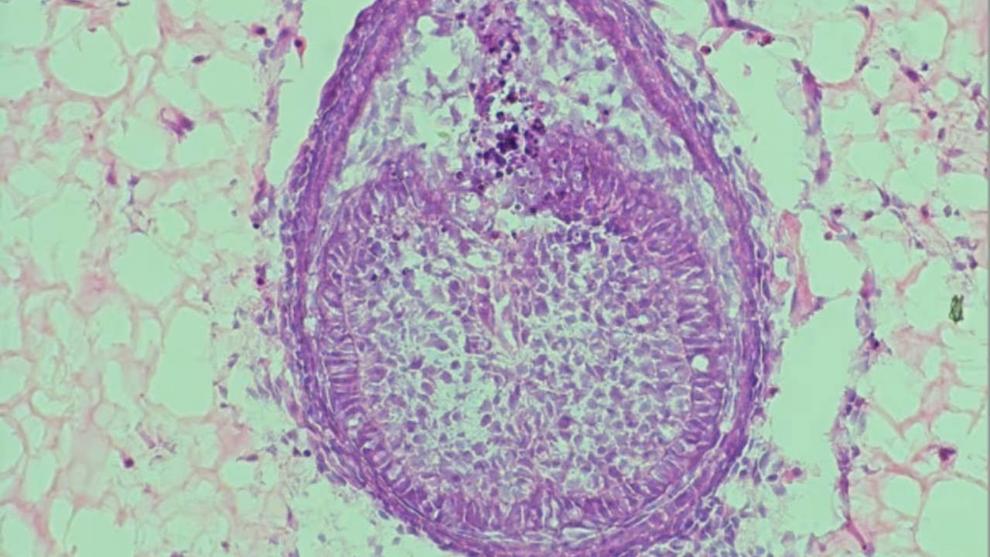

CNN International گزارش داد که پژوهشگران دانشگاه کینگز کالج لندن (King’s College London) گام بزرگی در مسیر تولید دندان‌های زیستی از سلول‌های انسان برداشته‌اند. این پیشرفت می‌تواند آینده‌ای را رقم بزند که در آن بیماران به‌جای کاشت ایمپلنت‌های فلزی، دندان‌های واقعی خود را دوباره رشد دهند.

دکتر آنا آنجلوا ولپونی (Ana Angelova Volponi) از کینگز کالج لندن، نزدیک به بیست سال است که روی رشد دندان‌ها در محیط آزمایشگاهی کار می‌کند. او در سال ۲۰۱۳ عضوی از تیمی بود که موفق شد از ترکیب سلول‌های انسان و موش، دندانی واقعی رشد دهد.

در تازه‌ترین پژوهش، ولپونی موفق شده است ماده‌ای بسازد که شرایط رشد دندان در آزمایشگاه را به محیط زیستی واقعی دهان نزدیک‌تر کند. این دستاورد، گامی مهم به‌سوی جایگزینی سلول‌های موش با سلول‌های انسانی در تولید دندان‌های آزمایشگاهی به‌شمار می‌آید.

به گفته ولپونی، ایده رشد دندان در محیط مصنوعی به دهه ۱۹۸۰ برمی‌گردد. در پژوهش سال ۲۰۱۳، او و تیمش نخستین بار سلول‌های لثه بزرگسال انسان را با سلول‌های پیش‌ساز دندان از جنین موش ترکیب کردند تا جوانه‌ای از دندان بسازند.

این محیط رشد که با عنوان «اسکفلد» (Scaffold) شناخته می‌شود، در شکل‌گیری دندان نقشی حیاتی دارد. تمرکز پژوهش اخیر ولپونی نیز بر توسعه همین ساختار بوده است. در حالی‌که نسخه ۲۰۱۳ از کلاژن ساخته شده بود، نسخه جدید از هیدروژل استفاده می‌کند؛ ماده‌ای پلیمری با درصد بالای آب که محیطی طبیعی‌تر برای رشد سلول‌ها فراهم می‌آورد.

چگونه دندان در آزمایشگاه رشد می‌کند؟

Xuechen Zhang، دانشجوی دکترا و همکار این پروژه، فرایند را این‌گونه توضیح می‌دهد:

«سلول‌های جنین موش را جمع‌آوری می‌کنیم، با هم ترکیب می‌نماییم و توده‌ای کوچک از سلول‌ها (Pellet) می‌سازیم. سپس آن را داخل هیدروژل تزریق کرده و حدود هشت روز رشد می‌دهیم.»